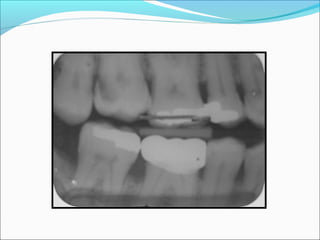

Indications ļ‚—Routine radiograph atregular dental checkups ļ‚—Proximal Caries ļ‚—Monitoring of progression of caries ļ‚—Overhanging restorations ļ‚—Diagnosis of Periodontal disease